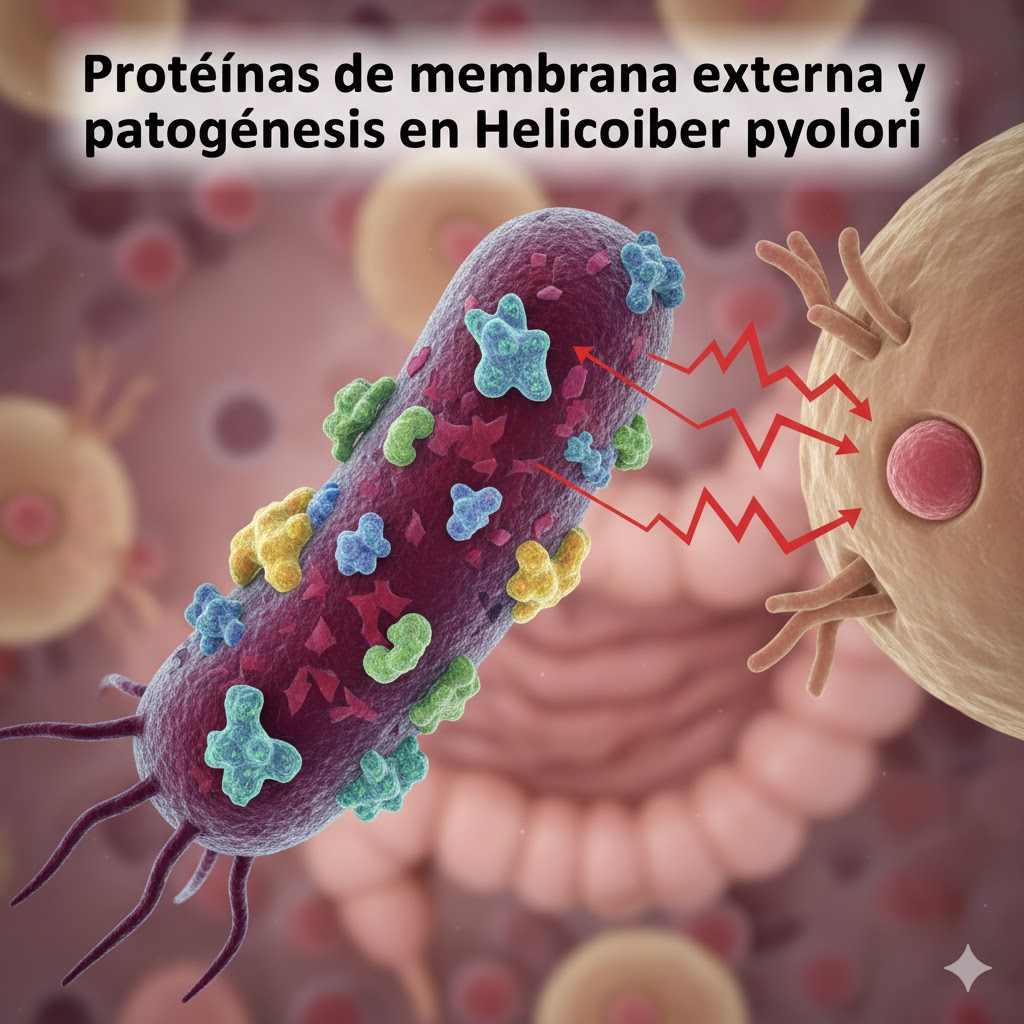

La asociación entre Helicobacter pylori y el espectro de cánceres digestivos. Esta revisión analiza el papel emergente de Helicobacter pylori más allá del estómago, destacando su asociación con distintos tipos de cánceres digestivos como el hepático, biliar, esofágico, colorrectal y pancreático. Aunque es un carcinógeno gástrico bien establecido, cada vez hay más evidencia que lo vincula con neoplasias extragástricas a través de mecanismos como la inflamación crónica y la acción de factores de virulencia. La solidez de estas asociaciones varía según el tipo de cáncer, siendo más consistente en los casos de cáncer hepático y biliar. Les invitamos a leer el artículo «Beyond the stomach: the association between Helicobacter pylori and the spectrum of digestive cancers», que explora el vínculo emergente entre H. pylori y diversos cánceres digestivos extragástricos. Un recurso esencial para actualizar su conocimiento sobre el impacto de esta bacteria en el cáncer hepático, biliar, esofágico, colorrectal y pancreático. 👉 ¡Acceda al artículo completo y profundice en los mecanismos subyacentes y las implicaciones terapéuticas! https://pubmed.ncbi.nlm.nih.gov/40964055/